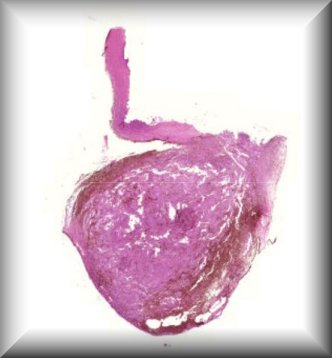

Francesc Tresserra (Guest): 26 year old male with history of Von Hipple Lindau syndrome. Enucleation of the left eye was performed. |